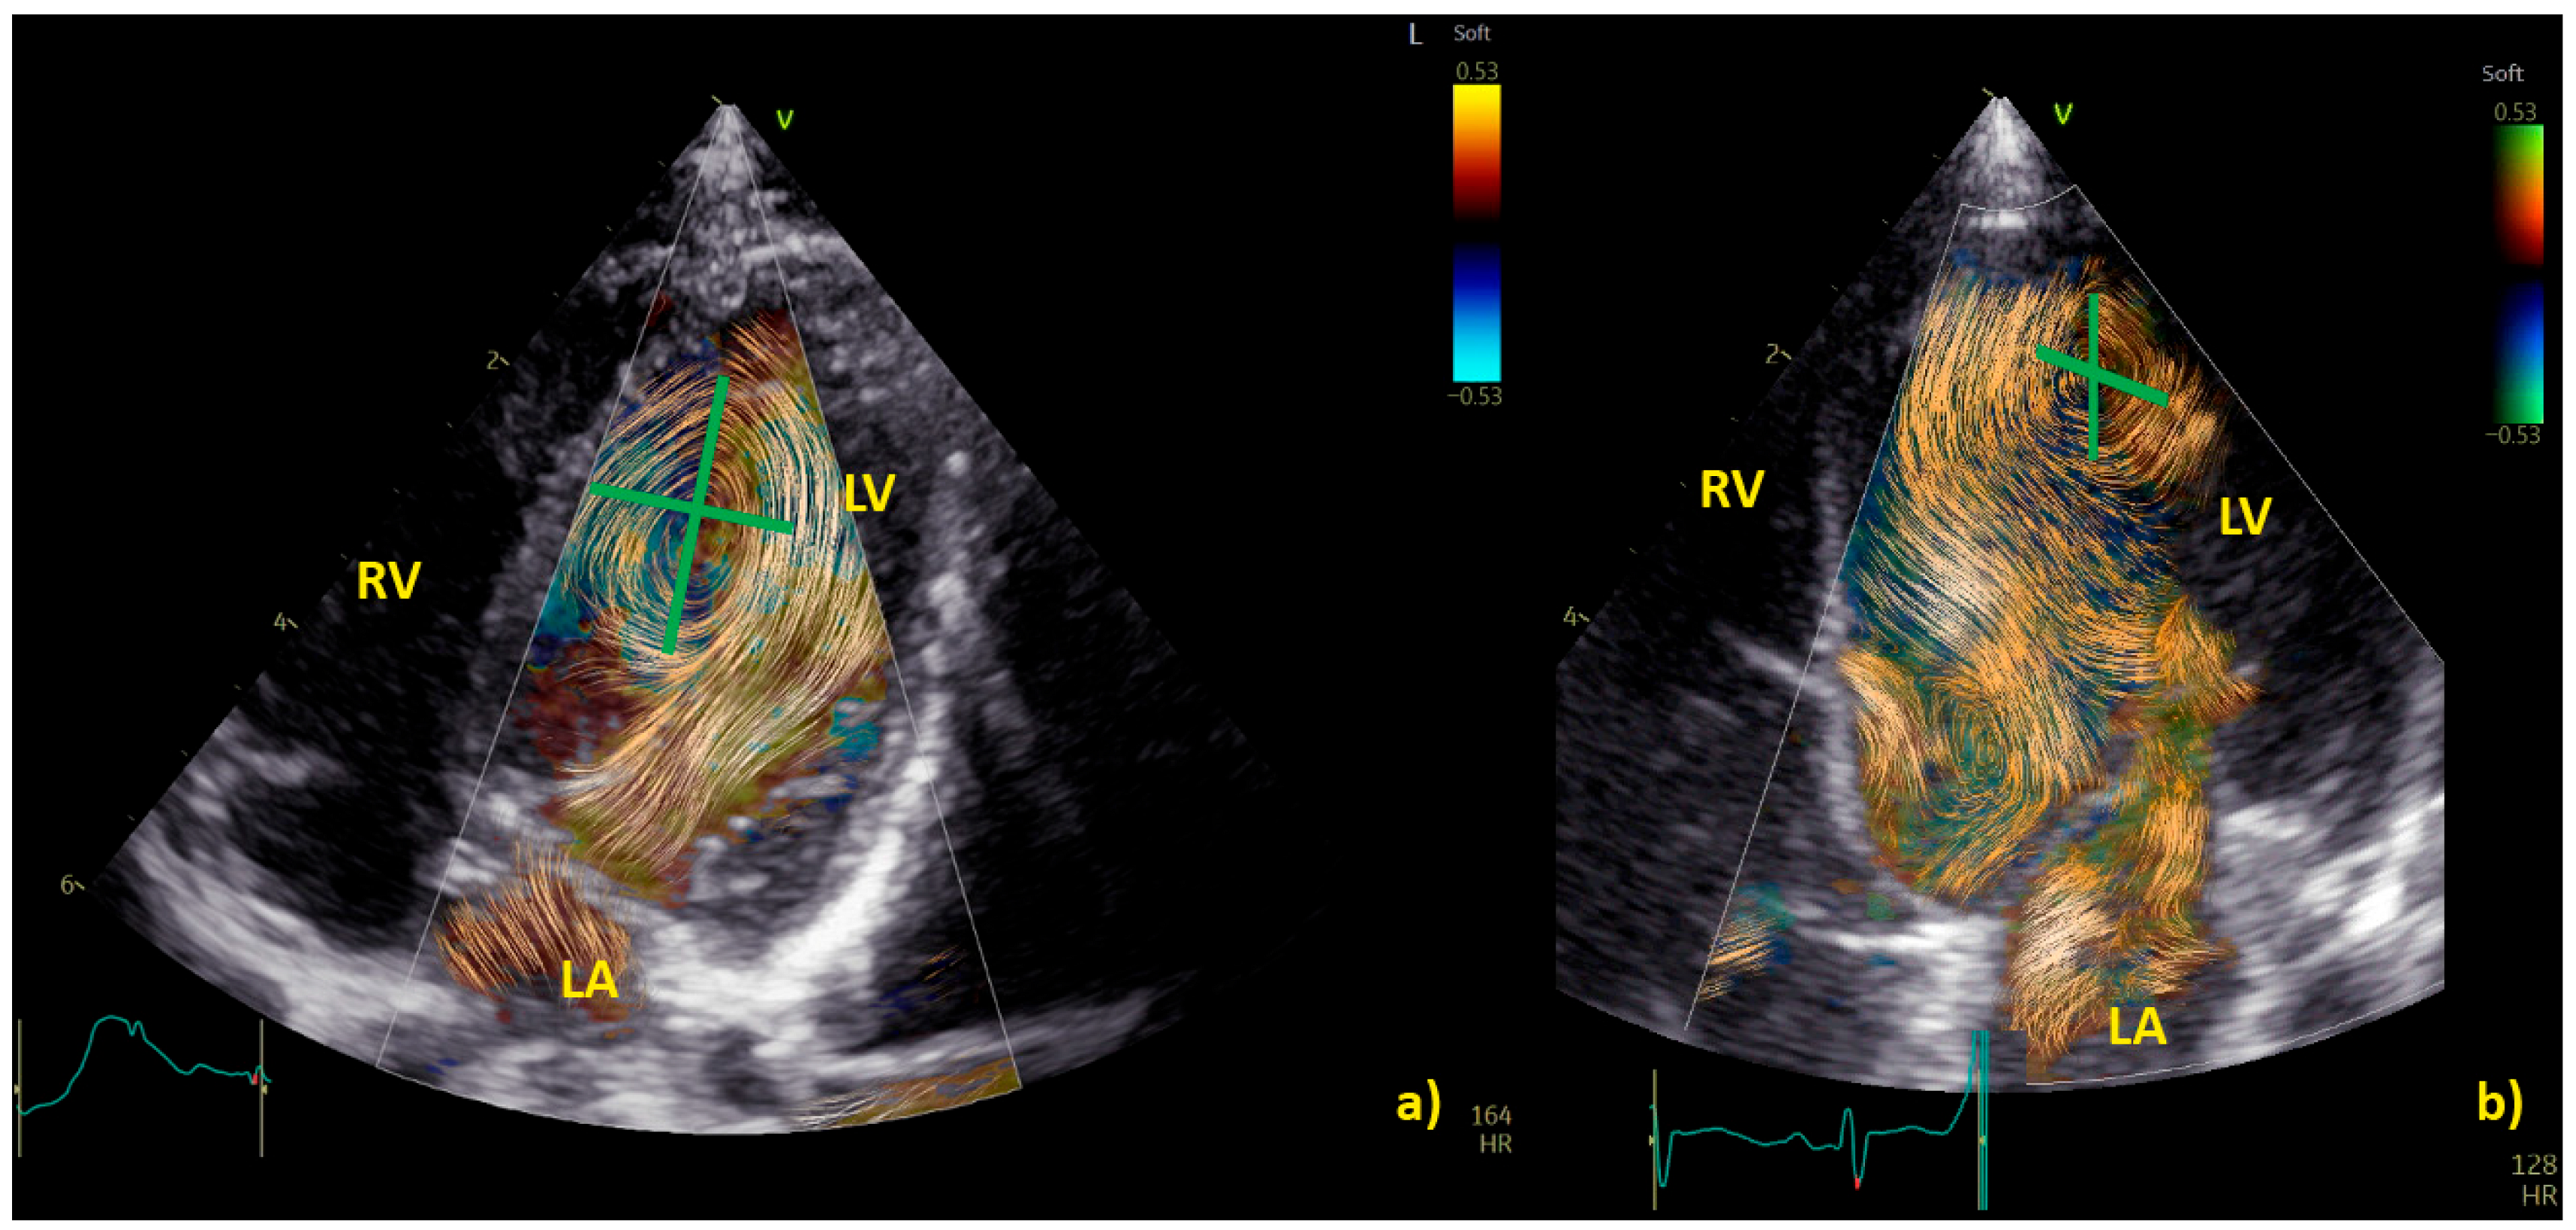

Examples of physiological and pathological left ventricular vortices are provided in Figure 2).

Figure 2. Comparison of left ventricle (LV) diastolic vortex in a healthy heart (a) and in a heart with left ventricular volume overload due to a significant patent arterial duct (b). BST images were acquired by zoom on an apical 4-chamber view, including both the interventricular septum and the mitral valve. Position of the vortex was calculated in relation to two lines: (1) a line from the ventricular apex to the mitral valve, and (2) a line from the IVS to the LV free wall. Vortex height was determined by measuring the longitudinal dimension of the main vortex relative to LV length, and vortex width as the horizontal dimension of the vortex relative to LV width. The vortex in (b) has a different size and position (further from the interventricular septum and with a larger area) compared to the healthy counterpart. LA = left atrium; LV = left ventricle; RA = right atrium; RV = right ventricle.